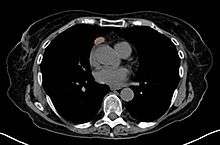

When a thymoma is suspected, a CT/CAT scan is generally performed to estimate the size and extent of the tumor, and the lesion is sampled with a CT-guided needle biopsy. Increased vascular enhancement on CT scans can be indicative of malignancy, as can be pleural deposits.[1] Limited biopsies are associated with a very small risk of pneumomediastinum or mediastinitis and an even-lower risk of damaging the heart or large blood vessels. Sometimes thymoma metastasize for instance to the abdomen.[3]